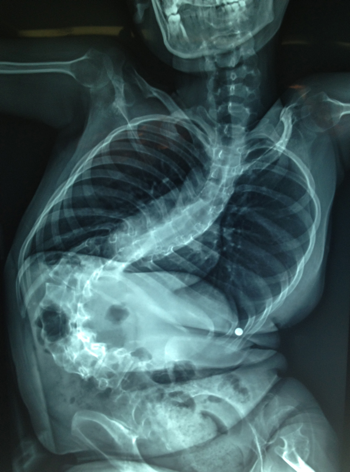

Nerve Assure is an Arizona based company that provides intraoperative neurophysiological monitoring (IONM) for physicians and hospitals. We offer reliable, high quality monitoring by certified technologists for a wide range of spinal, intracranial, cardiovascular, and peripheral nerve surgeries. Our mission is to provide the highest level of quality service to patients, physicians, and hospitals in order to optimize surgical outcome and minimize risk.

IONM has become a gold standard of care in the industry. The purpose is to reduce the risk to the patient of damage to the nervous system and provide functional guidance to the surgeon and anesthesiologist. IONM is used to localize neural structures, test the function of these structures, and for early detection of injury allowing for immediate corrective measures. Utilizing IONM reduces surgical risk by providing critical information to the surgeon during the surgery to reduce or eliminate neurological deficits.